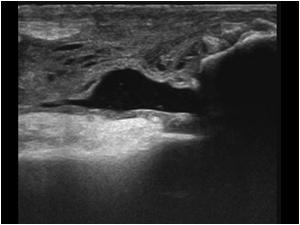

Ultralyd er god til at verificere

diagnosen:

Kan laves dynamisk, hvor knæet bevæges samtidigt.